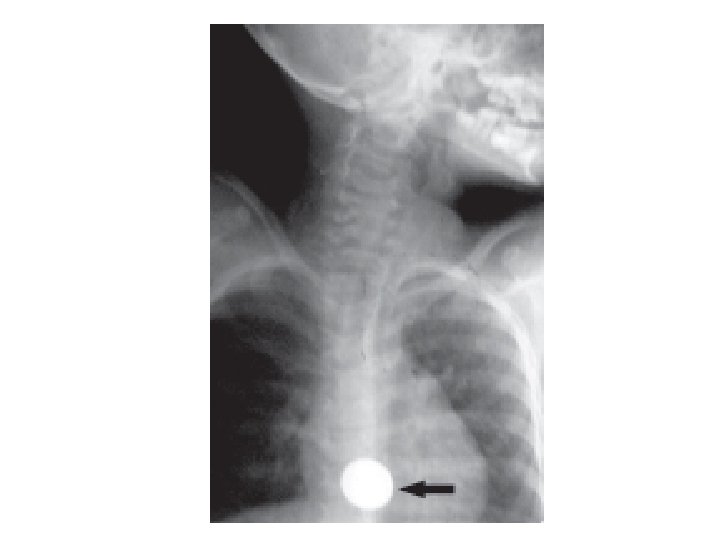

Foreign Body in the Oesophagus • Common sites are the cervical constriction, broncho-aortic constriction and diaphragmatic constriction. • Common foreign object: coin, dentures, bone • Treatment: antibiotics, endoscopic removal, thoracotomy